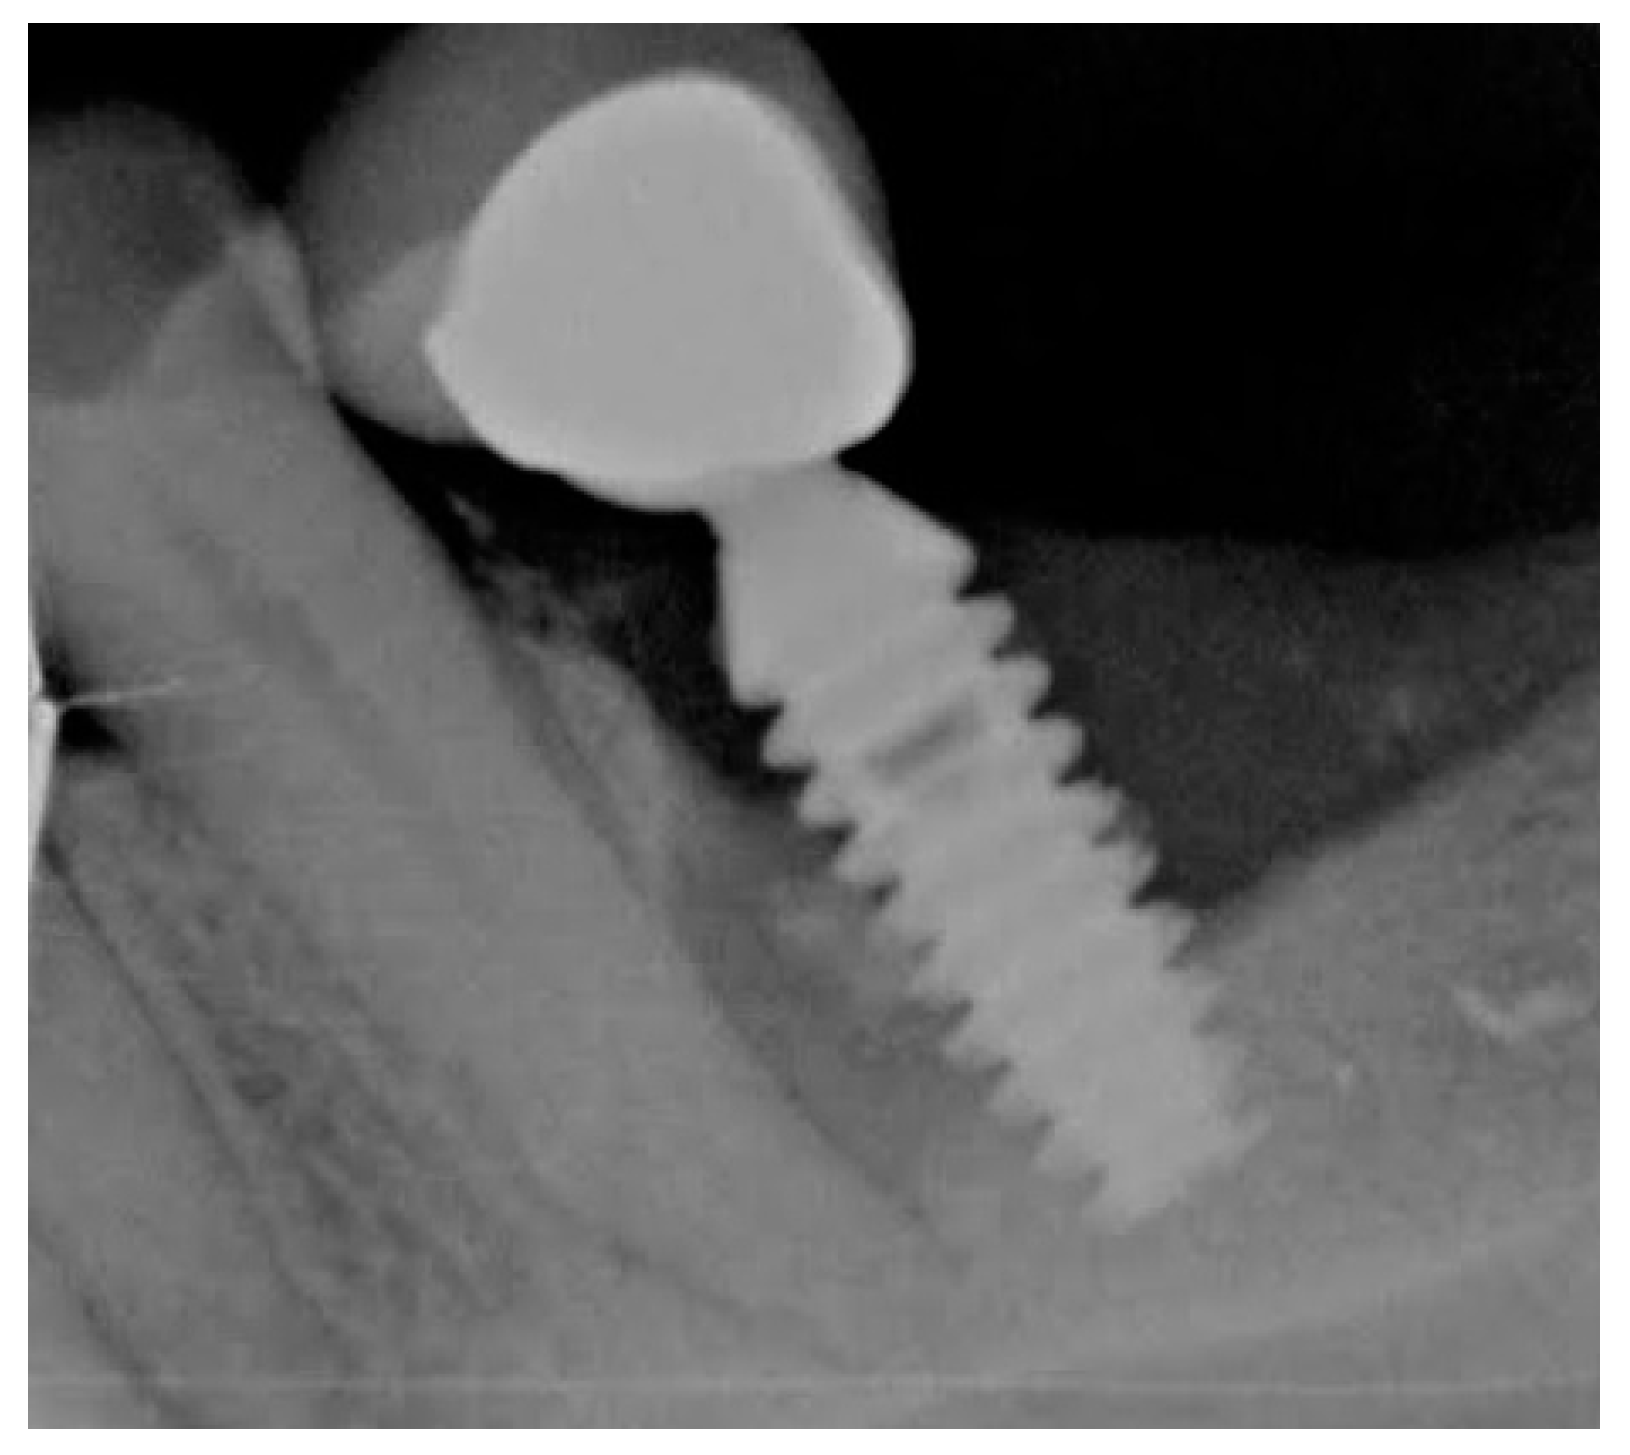

4.2.3. Dental Implants and Perimplantitis